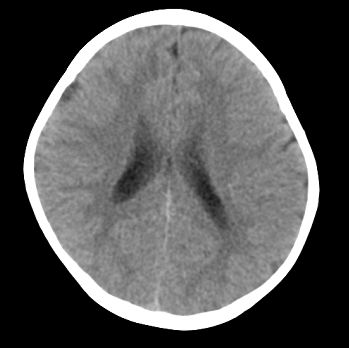

以下是引用22222222在2008-6-9 21:03:00的发言:[br]病灶周围见脑组织包绕,上部可见等或稍高密度壁环绕,壁且见小点钙化-----考虑皮样囊肿或表皮样囊肿可能,但侧脑室颞角内病灶不排除.